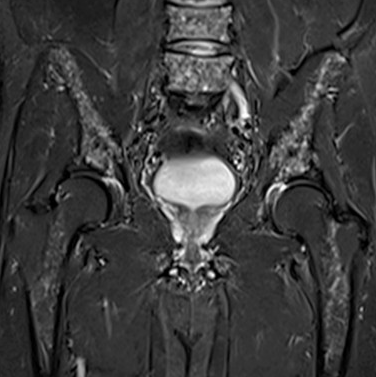

Mazabraud Syndrome

• Fibrous dysplasia + intramuscular myxomas

• Intramuscular myxomas are hypo T1, Hyper T2 and variable enhancement

• Most commonly of the pelvis and lower extremity

• More common on right side

• GNAS1 gene mutation —> 20q13.2-q13.3

• Associated with McCune Albright syndrome